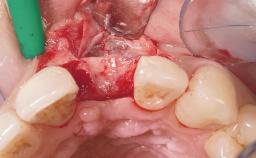

Late Placement of an Implant in a Maxillary Left Central Incisor Site

A 36-year-old female patient was referred for the replacement of the upper left central incisor (tooth 21), which had fractured. Although the tooth had been asymptomatic for many years, the crown began to loosen, at which time she presented to her dentist for an assessment. Teeth 21 and 22 had both been endodontically treated many years previously. She was a healthy individual and a non-smoker.

| Bone Augmentation | Horizontal|Staged |

| Augmentation Materials | Xenogenous|Membrane |

| Bone Volume | Deficient horizontally, requiring prior grafting |